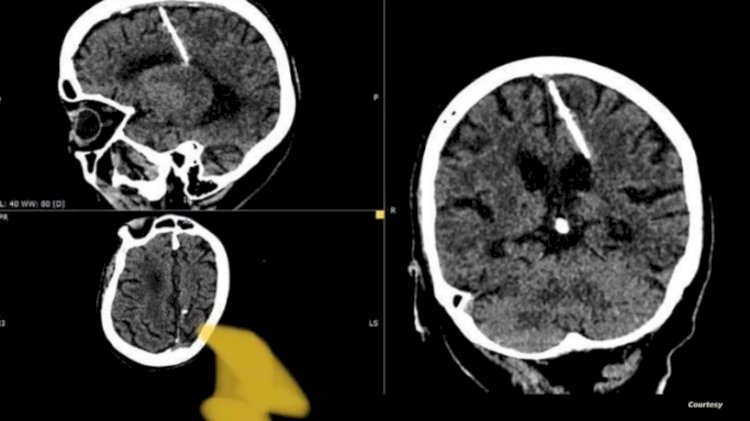

صورة الاشعة المقطعية

عثر أطباء خلال فحص بالتصوير المقطعي على إبرة بطول ثلاثة سنتيمترات موجودة منذ ثمانين عاماً داخل دماغ امرأة مسنّة في أقصى الشرق الروسي.

ويعتقد الأطباء أن المرأة تعرضت لمحاولة قتل فاشلة نفذها والداها خلال طفولتها، وقالوا إنهم لن يحاولوا إزالة الإبرة خشية أن يفاقم ذلك حالتها.

وقالت إدارة الصحة المحلية لقد اخترقت الإبرة الفص الجداري الأيسر، لكن لم يكن لها التأثير المقصود، إذ نجت الفتاة.